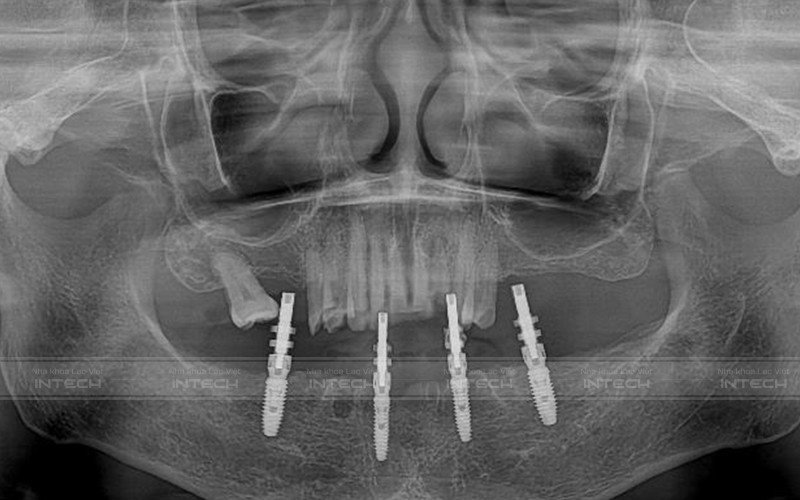

Dựa trên dữ liệu phim chụp CT Conebeam, dữ liệu Scan iTero Element 5D và kết quả thăm khám lâm sàng, các bác sĩ đã đưa ra kế hoạch điều trị cụ thể cho Cô Hà:

• Nhổ bỏ toàn bộ các răng lung lay hàm dưới

• Ghép xương vùng răng bị tiêu xương

• Cấy ghép Implant All-On-4 toàn hàm dưới

Hình ảnh phim chụp sau cấy ghép Implant của cô (Ảnh: Nha khoa Lạc Việt Intech)

So với trồng implant đơn lẻ thì kỹ thuật trồng răng all-on-4 / all-on-6 sẽ phức tạp hơn rất nhiều, đòi hỏi bác sĩ phải được đào tạo bài bản về chuyên môn và kinh nghiệm thực tế. Việc ứng dụng công nghệ trồng răng Safe-Tech trong quá trình điều trị đã giúp bác sĩ có thể lựa chọn những vị trí xương hàm tốt nhất để đặt chân răng Implant. Đồng thời đảm bảo xuyên suốt hành trình trồng răng Implant diễn ra nhanh chóng, an toàn, không đau, nhanh lành thương nhanh.